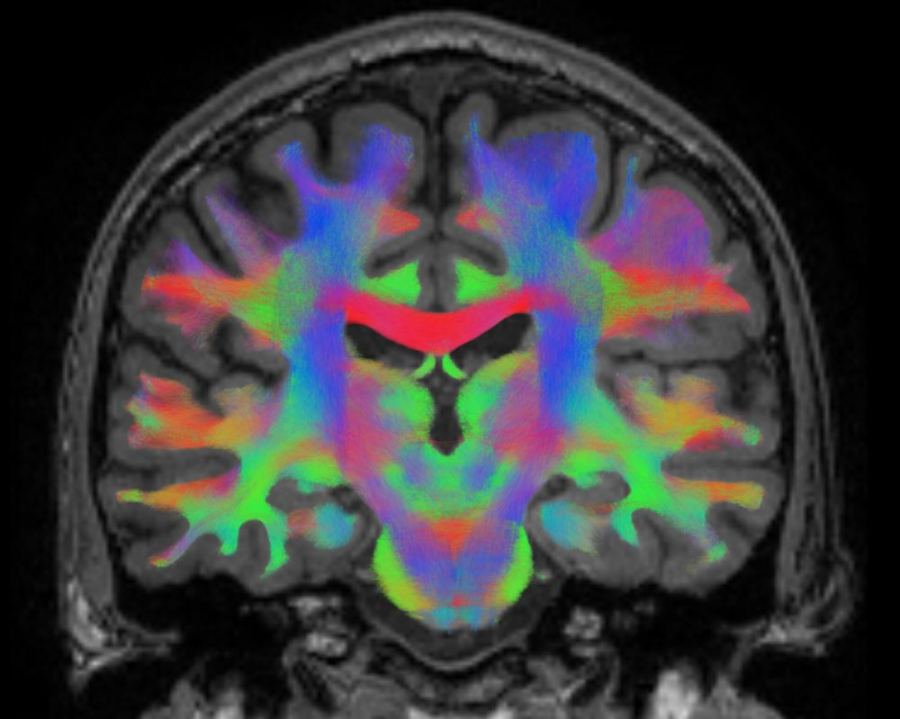

To understand how brains adapt, the Belgian research teams did magnetic resonance imaging (MRI) scans of 16 cosmonauts' brains. Some were taken before the missions while they were "at rest". That is, they didn't do any tasks at all during the scans. Then, after their time in space, the team took several more scans to see what changes existed and how long they persisted. The "resting-state functional MRI" technique enabled the researchers to investigate the brain's default and "post-flight" states.

The results showed that the brain's functional connectivity was definitely different after the flights. That describes a state where activity in some areas correlates with activities in other parts. According to the two study leaders, Steven Jillings and Floris Wuyts (University of Antwerp), space traveler brains showed marked differences in pre- and post-flight scans. "We found that connectivity was altered after spaceflight in regions which support the integration of different types of information, rather than dealing with only one type each time, such as visual, auditory, or movement information', they said. "Moreover, we found that some of these altered communication patterns were retained throughout eight months of being back on Earth. At the same time, some brain changes returned to the level of how the areas were functioning before the space mission."